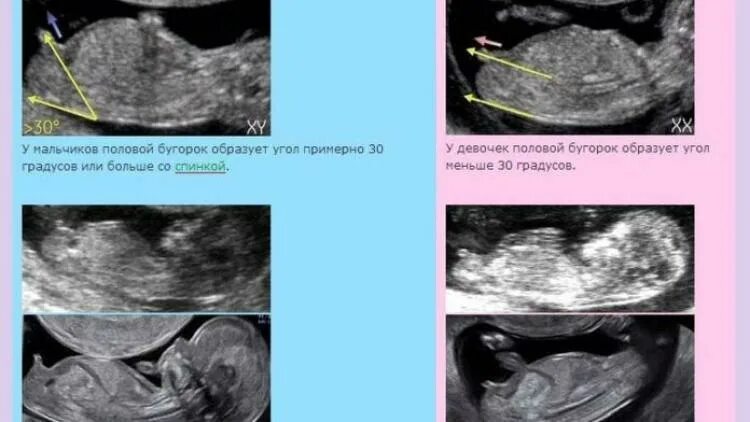

15 неделя можно узнать пол ребенка